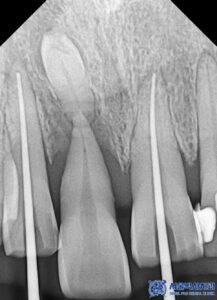

결국, 해당 치아는 살릴 수 없는 상태였기에

발치를 진행하기로 하였으며,

치근낭(치아 뿌리 주변에 형성된 염증 조직)도

함께 제거하고 염증으로 잇몸뼈가 녹은 부위는

잇몸뼈를 이식하여 잇몸이

꺼져 보이지 않도록 진행하기로 하였습니다.

단 치아를 삭제한 후 크라운을 수복해야 하므로

치아가 시리지 않도록 신경치료를 진행하여

최대한 자연치아를 보존하기로 하였습니다.

또한 신경치료에서 가장 중요한 것은 치아 내부를

얼마나 깨끗하게 소독하고,

이후 어떤 재료로 신경관을 채우느냐입니다.

대부분의 치과에서는 신경치료 후 신경관을 고무 성분

(가타퍼차, Gutta-Percha)으로

충전하는 방식으로 마무리합니다.

하지만 서울박사치과에서는

더욱 철저한 치료를 위해 MTA

(바이오세라믹 재료)를 사용합니다.